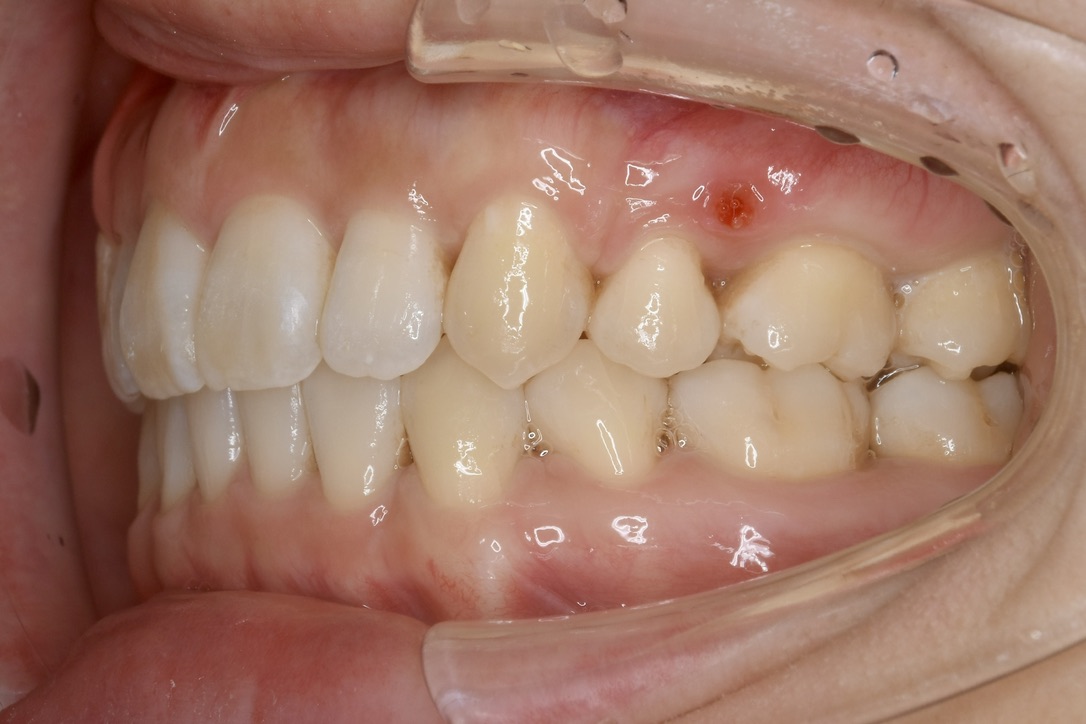

| 主訴 | 前歯の隙間が気になる。 |

|---|---|

| 診断名・主な症状 | 左側犬歯のクロスバイトを伴う空隙歯列 |

| 年齢 | 22歳 |

| 治療内容 | 上の歯のスペースを閉じつつ、下の歯を後ろに下げました。 |

| 使用装置 | マウスピース矯正装置(インビザライン) |

| 抜歯部位 | 抜歯なし |

| 治療期間 | 1年10ヶ月 |

| 通院回数 | 14回 |

| 費用 | 86万円程度(税別) |

| リスク・副作用 | 痛み、歯肉退縮、歯根吸収、抜歯に伴う出血や腫れが生じることがあります。 |